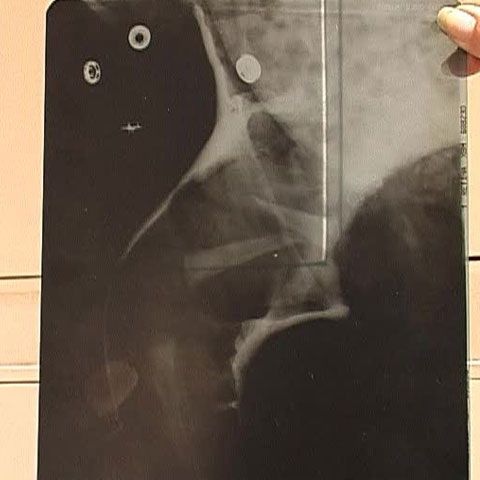

Pentru că vedeau că pe băieţel îl doare ceva, părinţii au venit cu el la Bucureşti. Radiografia a arătat o fractură de femur.